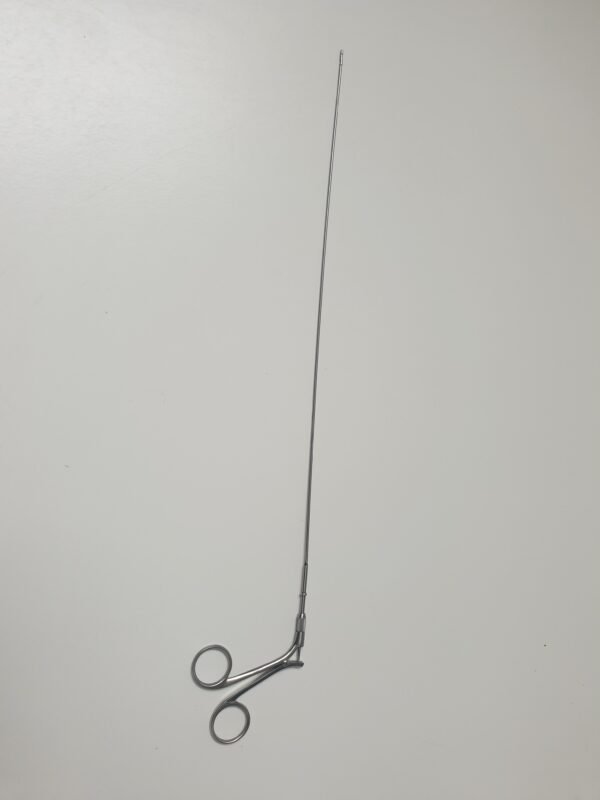

Zustand: Ungeprüft

• Dieses HF Kabel wurde nicht vollständig getestet und könnte daher Funktionsfehler aufweisen.

• Die Bilder sind Teil der Beschreibung – Sie erhalten genau das, was abgebildet ist.

• Eine Besichtigung und Abholung sind nach Absprache möglich.

Hinweis: Aufgrund gesetzlicher Bestimmungen werden alle Geräte als defekt für Bastler oder Ersatzteilspender verkauft, auch wenn sie funktionsfähig sind. Der Käufer wird ausdrücklich darauf hingewiesen, dass er bei der Inbetriebnahme die Vorschriften des Medizinprodukte-Durchführungsgesetzes (MPDG) sowie der Medizinprodukte-Betreiberverordnung (MPBetreibV) einzuhalten hat. Eine sicherheitstechnische Kontrolle des Geräts muss wie vorgeschrieben durchgeführt werden. Für die Einhaltung ist der Käufer selbst verantwortlich.